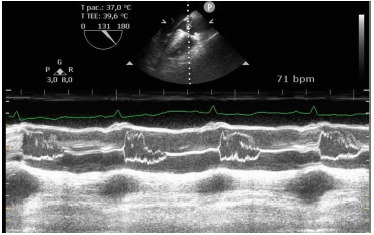

Identifique a condição patológica evidenciada na figura a seguir.

Provas